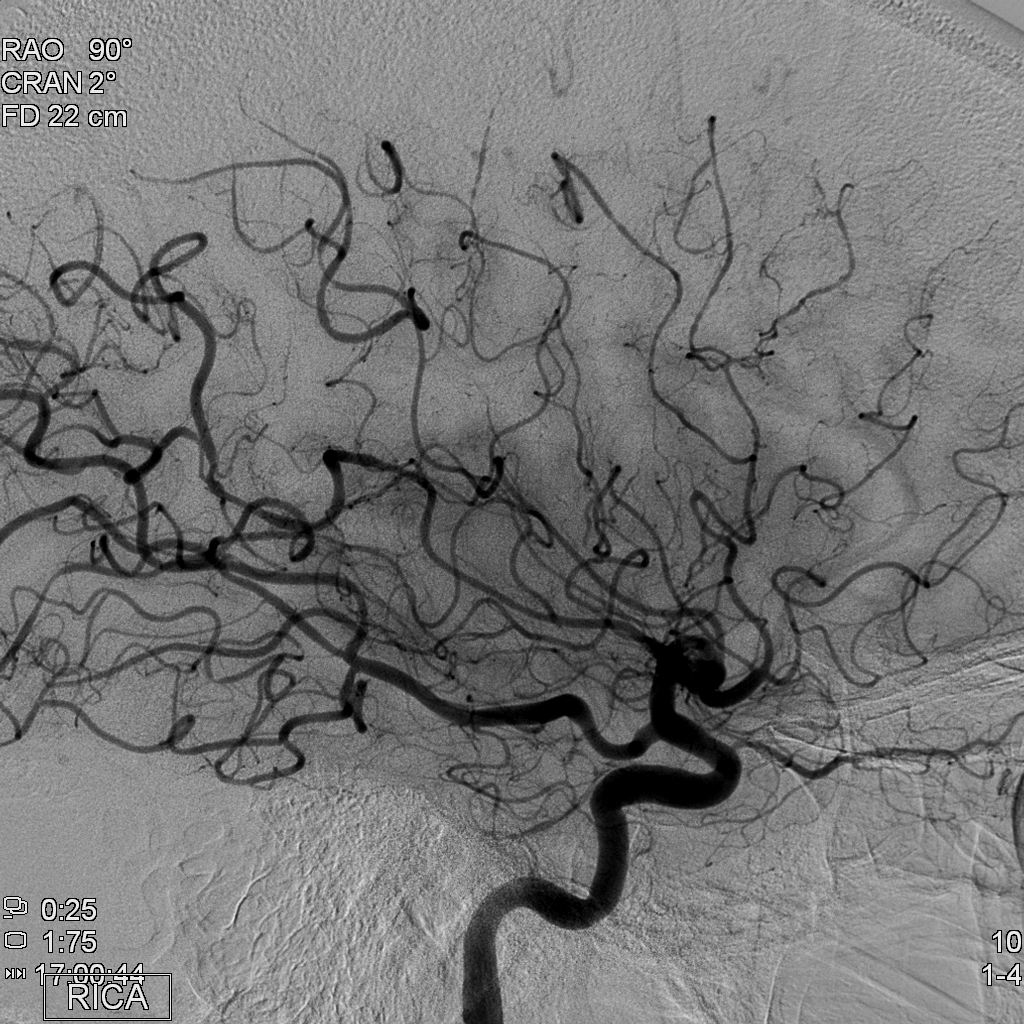

Exon-screening in Reversible Cerebral Vasoconstriction (RCVS)

Objectives: To investigate the genetic basis of RCVS using exome capture and deep sequencing.